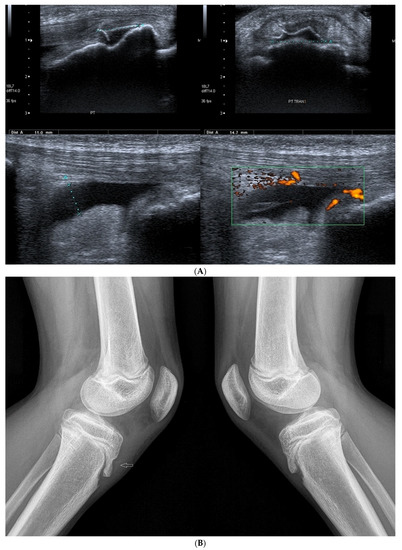

Basic Differences and Most Common Findings in Ultrasound Examinations of Musculoskeletal System in Children: A Narrative Literature Review

by Tomasz Poboży, Wojciech Konarski, Karolina Piotrowska-Lis, Julia Domańska, Kamil Poboży and Maciej Kielar

Healthcare 2022, 10(10), 2010; https://doi.org/10.3390/healthcare10102010 - 12 Oct 2022

We present basic differences in the musculoskeletal ultrasound examinations between adults and children. Examiners who deal with adults on a daily basis have shared concerns about examining children. Such concerns may arise from the different approach to child ultrasounds, but they also come [...] Read more.

We present basic differences in the musculoskeletal ultrasound examinations between adults and children. Examiners who deal with adults on a daily basis have shared concerns about examining children. Such concerns may arise from the different approach to child ultrasounds, but they also come from differences in anatomical characteristics according to developmental age. We discuss the presence of growth plates, as well as non-mineralized parts of the bones. We also refer to the pathologies most often found in ultrasounds in early developmental stages. In the PubMed database, the set of keywords: “msk ultrasound in children”, “pediatric msk sonoanatomy”, “coxitis fugax”, “pediatric Baker’s cyst”, “Baker’s cyst ultrasonography”, “bone septic necrosis in ultrasonography”, “ultrasonography in juvenile idiopathic arthritis”, and “ultrasonography in juvenile spondyloarthropathies”, was used to identify a total of 1657 results, from which 54 was selected to be included in the article. We discuss the problem of osteochondritis dissecans, Osgood-Schlatter disease, examples of ligament injuries (especially in relation to the knee and ankle joints), exfoliation of growth cartilages, osteochondroma, exudates and inflammations affecting joints, and Baker’s cysts. In this way, we have collected useful information about the most common diseases of the musculoskeletal system in children. Full article

Show Figures

Figure 1